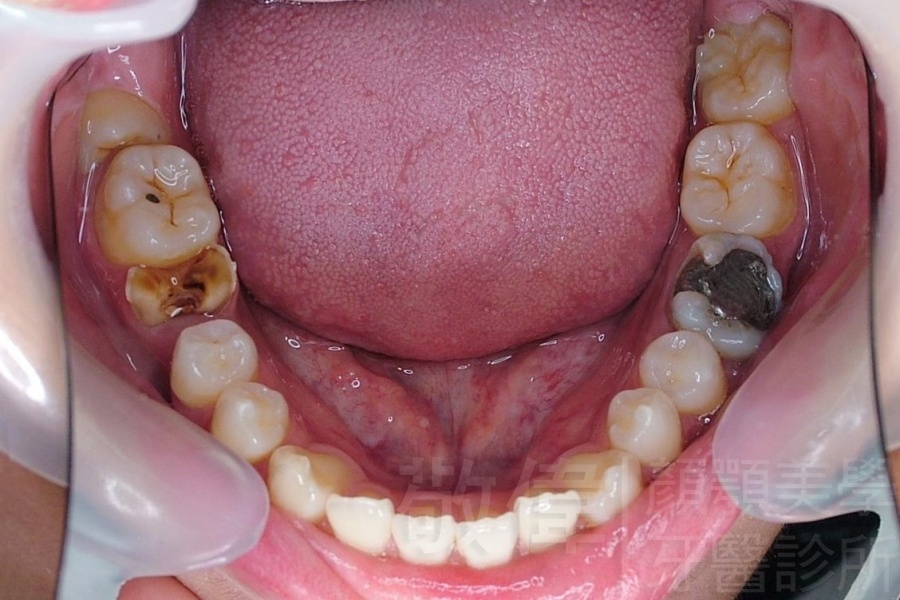

齒顏矯正/戽斗、亂牙、爛牙,變身 免植牙的健牙美女

變臉矯正,原來戽斗妹跟大歪臉變成自信正妹

經由本院3D數影X光影像儀分析、與3D齒顎顏矯正技術,再配合口腔顎面正顎專科醫師施以正顎手術治療,雙方共同合作,使患者臉部外觀有很好的改善,大歪變小歪,產生了天南地北的大改變,她的人生也整個變得不一樣。